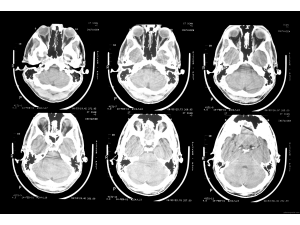

Китайци са извършили първата в историята трансплантация на глава

Китайски лекари са направили първото в историята успешно присаждане на човешка глава, съобщи италианският хирург Серджо Канаверо, който още през 2015 г. заяви, че се подготвя да извърши такава операция.Първата трансплантация е направена върху труп. Следващата стъпка е операция на глава от донор с регистрирана мозъчна смърт, ...